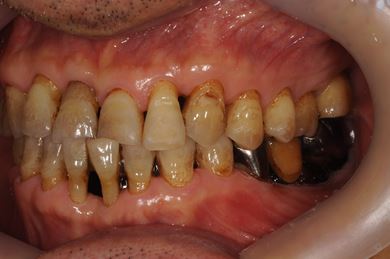

抜歯即日スピードインプラント治療+セラミック治療+歯肉遊離移植術

| 性別/年齢 | 男性 / 64歳 | ||||||||||||||||||||||||||||||||

| 主訴 | 左最奥の下部ブリッジが不安定になっており、奥2本のインプラントを考えたい。 | ||||||||||||||||||||||||||||||||

| 治療内容 | インプラント4本(抜歯即日スピードインプラント)、メタルボンドセラミッククラウン5本、ハイブリッドセラミッククラウン1本(ハイブリッドセラミック用土台1本) | ||||||||||||||||||||||||||||||||